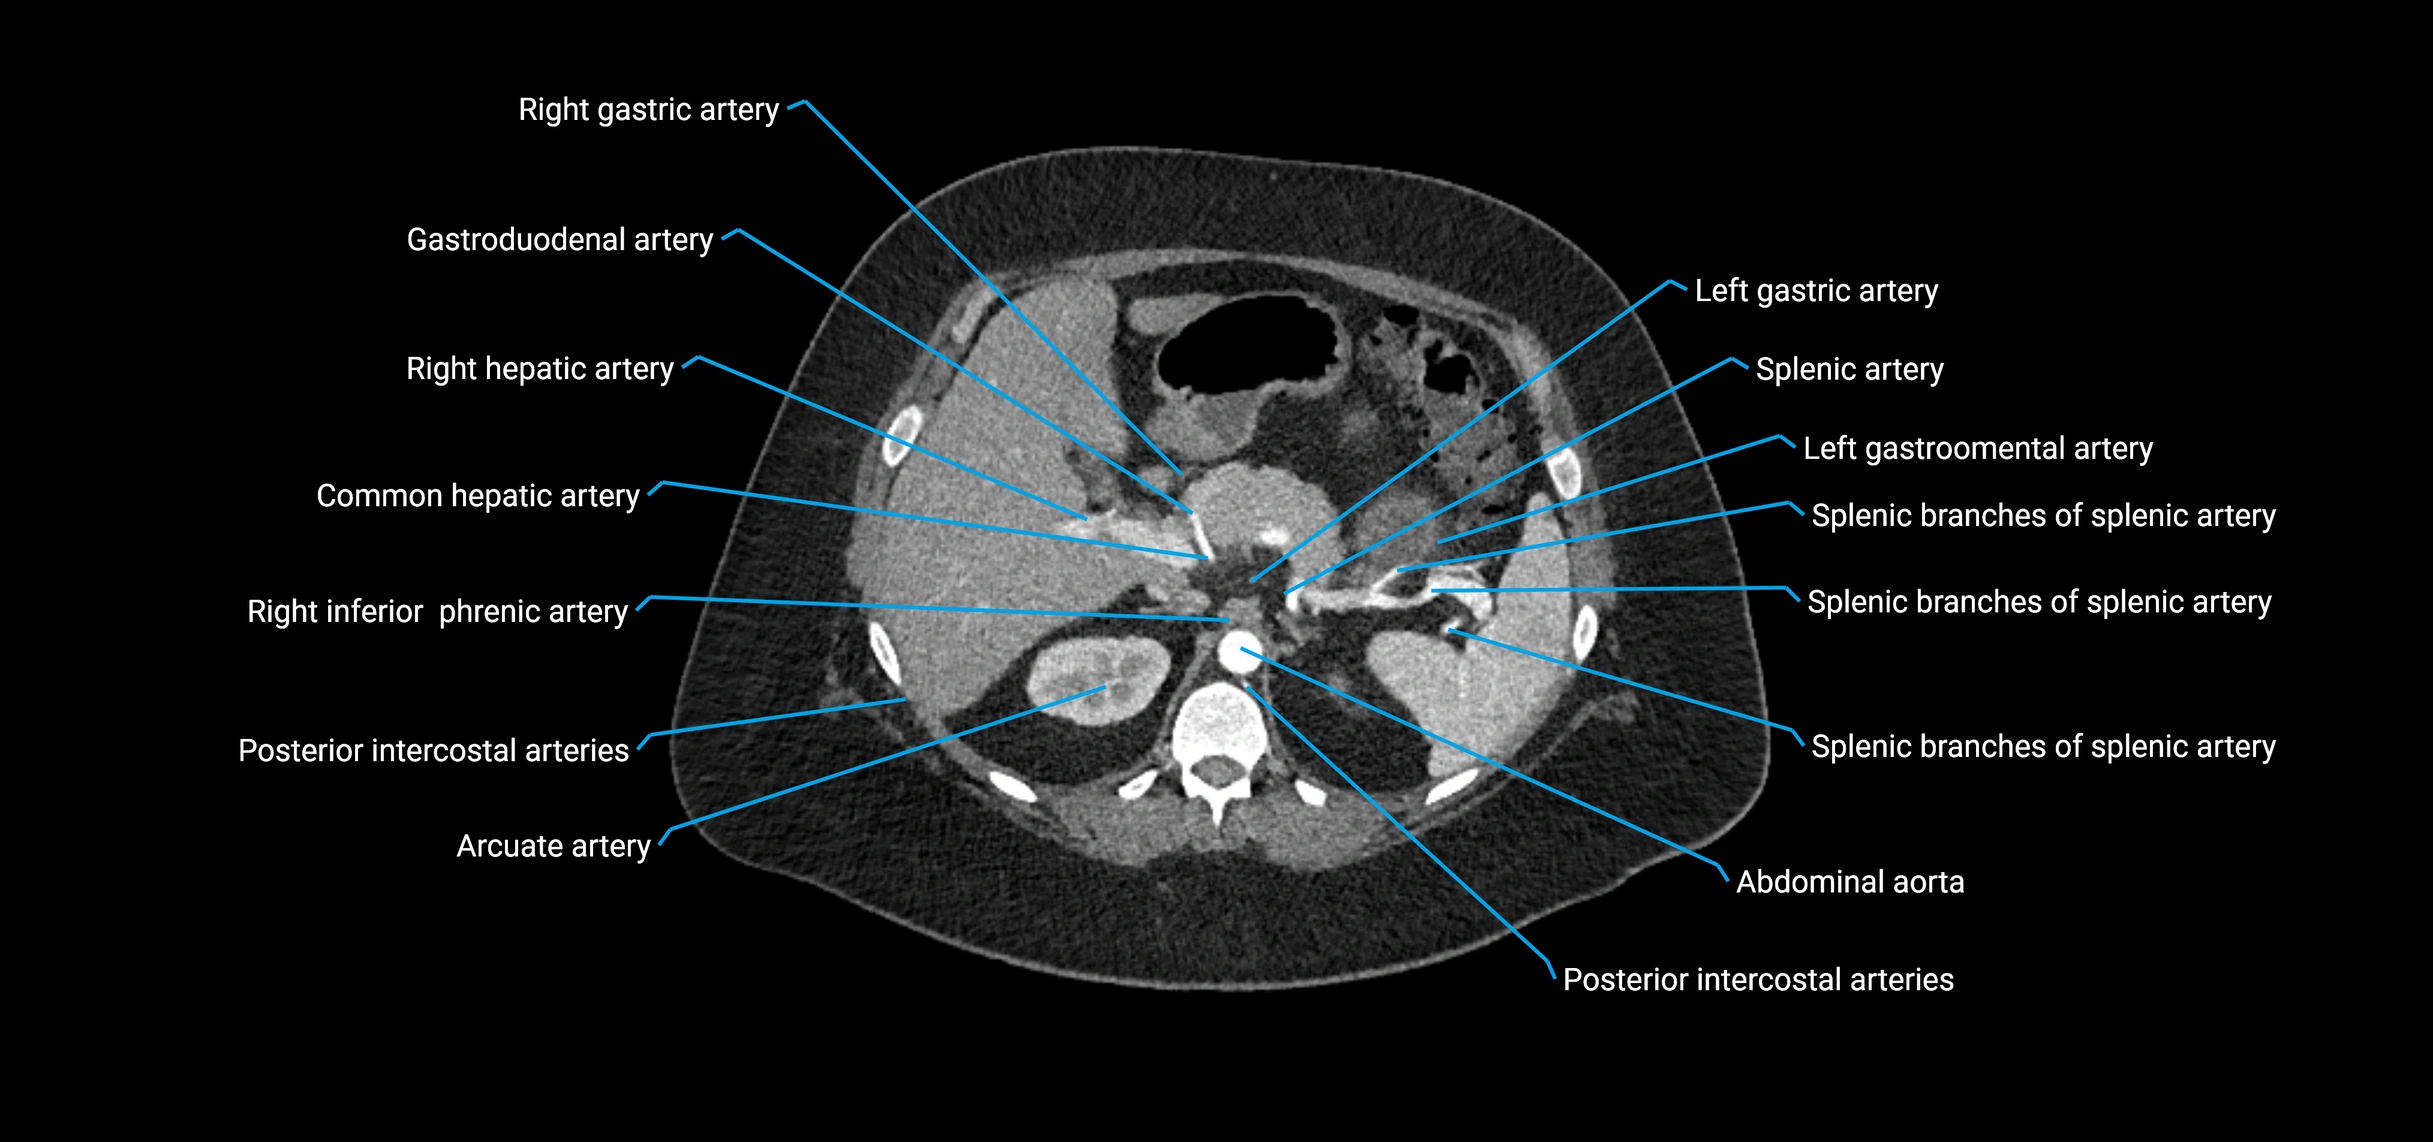

The abdominal aorta is the continuation of the thoracic aorta, beginning at the level of the aortic hiatus of the diaphragm (T12 vertebra) and terminating at the level of the L4 vertebra where it bifurcates into the right and left common iliac arteries. It lies slightly to the left of the midline and courses anterior to the vertebral bodies, surrounded by the retroperitoneal structures of the abdomen.

The abdominal aorta gives off numerous visceral and parietal branches, supplying the abdominal organs, pelvic structures, and lower limbs. It is the main conduit of oxygenated blood from the heart to the abdomen and lower body. The aorta is clinically significant as the common site of aneurysm, dissection, atherosclerosis, and traumatic injury.

Branches

• Unpaired visceral branches: celiac trunk, superior mesenteric artery (SMA), inferior mesenteric artery (IMA)

• Paired visceral branches: middle suprarenal arteries, renal arteries, gonadal arteries (testicular or ovarian)

• Parietal branches: inferior phrenic arteries, lumbar arteries, median sacral artery

• Terminal branches: right and left common iliac arteries

CT Appearance

Non-contrast CT:

• Appears as a tubular soft tissue structure anterior to vertebral bodies

• Calcified atherosclerotic plaques appear as hyperdense foci along the wall

• Useful for screening abdominal aortic aneurysm (AAA) size and mural calcification

Contrast-enhanced CT (CTA):

• Gold standard for abdominal aortic imaging

• Provides excellent detail of lumen, wall, aneurysm, thrombus, and branch vessels

• Multiplanar and 3D reconstructions help in aneurysm measurement, stent graft planning, and dissection evaluation

• Detects acute rupture, traumatic injury, or occlusion with high sensitivity